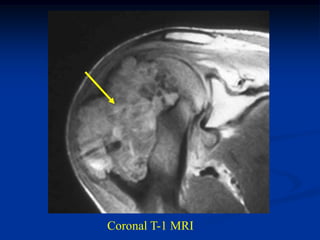

Case #120

38 year female

enchondroma

distal femur

Coronal T-1 MRI